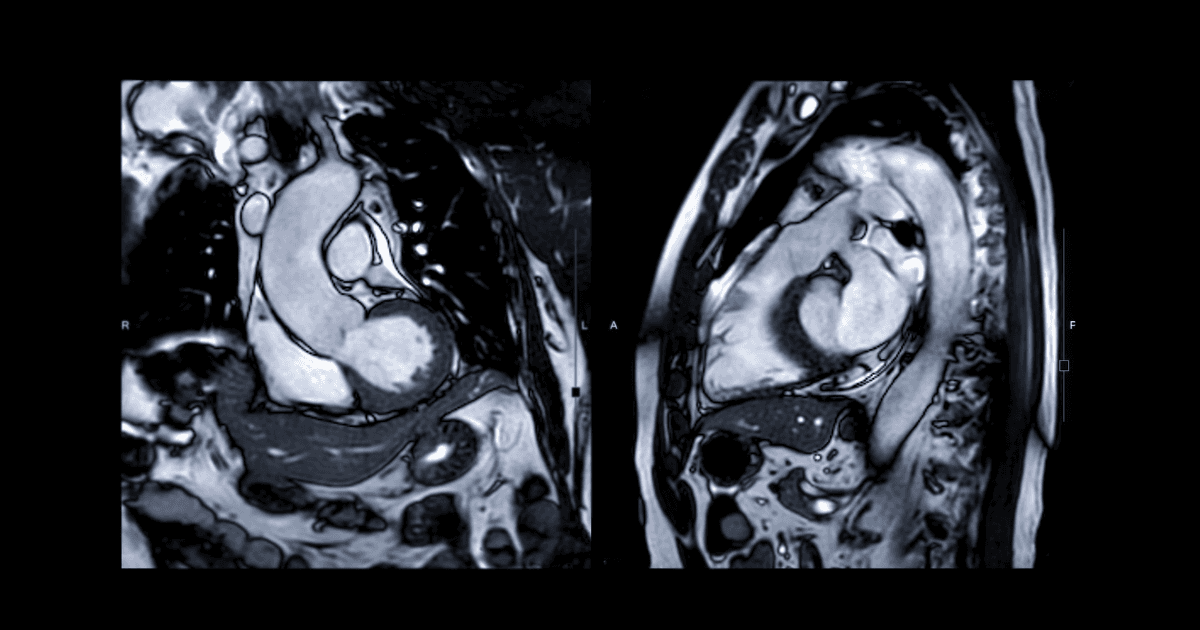

Cardiac MRI Inference from ECG

2026Ongoing research with MIT's Computational Cardiovascular Research Group on representation learning for cardiology—predicting MRI-relevant cardiac phenotypes from ECG-derived signals. Building the data pipeline, modeling stack, and evaluation framework focused on generalization, failure modes, and clinical interpretability. The lab uses machine learning and signal processing to turn clinical signals like ECGs into predictive computational biomarkers and risk models that guide clinical decisions.